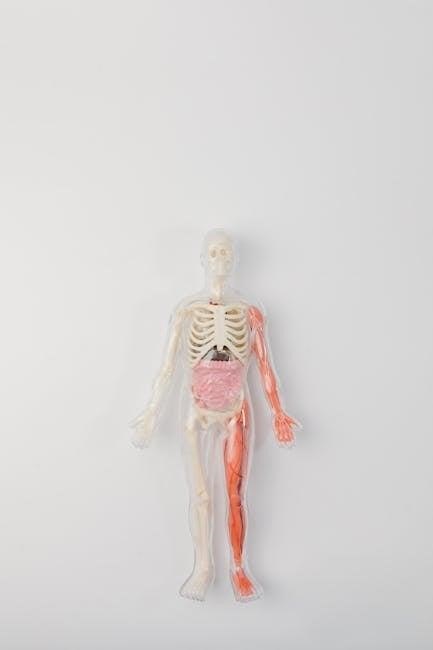

Anatomy & Physiology Coloring Workbooks are educational tools designed to aid in the understanding of the human body’s structure and function. They present detailed illustrations of anatomical structures – bones‚ muscles‚ nerves‚ organs‚ and systems – as line drawings‚ ready for students to color.

Unlike passively reading textbooks‚ coloring requires active participation‚ forcing students to identify and differentiate between various anatomical components. This hands-on approach is particularly beneficial for visual learners. The workbooks cover a broad range of topics‚ from basic cell biology to complex organ systems‚ making them suitable for various levels of study.

Inclusion of Physiological Concepts

A superior anatomy & physiology coloring workbook‚ especially in PDF format‚ transcends mere anatomical illustration by integrating physiological principles. It’s not enough to simply color a heart; the workbook should explain how the heart functions – cardiac cycle‚ blood flow‚ and electrical conduction.

Look for workbooks that present physiological information alongside anatomical structures. This could include brief explanations of organ functions‚ descriptions of cellular processes‚ or clinical correlations. The best resources connect structure to function‚ demonstrating why a particular anatomical feature exists and how it contributes to overall body homeostasis.